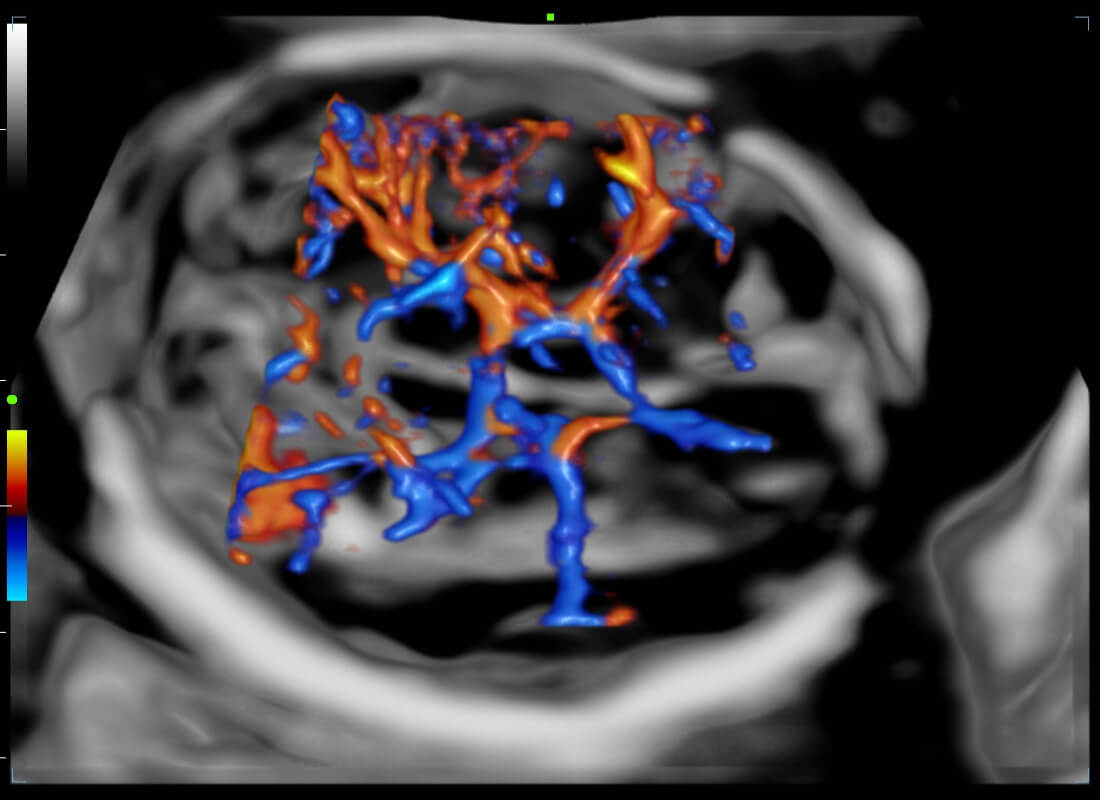

Central nervous system (CNS) malformations are one of the most common congenital abnormalities. Unfortunately, due to imaging limitations such as poor fetal position, acoustic shadowing, and operatorsŌĆÖ poor scanning skills, the MSP is particularly difficult to find in a 2D ultrasound. In this case, a faster and more user-friendly method, which automatically displays the standard planes together with the required measurements in a fetal CNS examination, could significantly boost both the quality and efficiency of clinical diagnoses.?NuewaŌĆÖs intelligent solution of fetal brain can realize automatic acquisition of brain volume data based on intelligent recognition of CNS application scenarios, intelligent generation of four fetal brain standard planes including MSP, automatic measurement of CNS biological items and automatic evaluation of fetal brain volume. More importantly, Nuewa's leading color Doppler technology can provide a clear and sensitive dynamic display of blood flow in the tiny vessels.